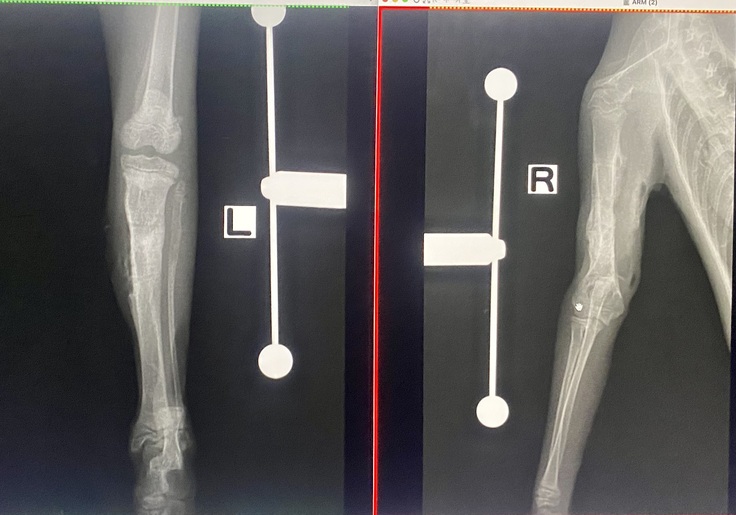

←左足 右上腕→

金属のスクリューも全て外してもらうことができました🎉